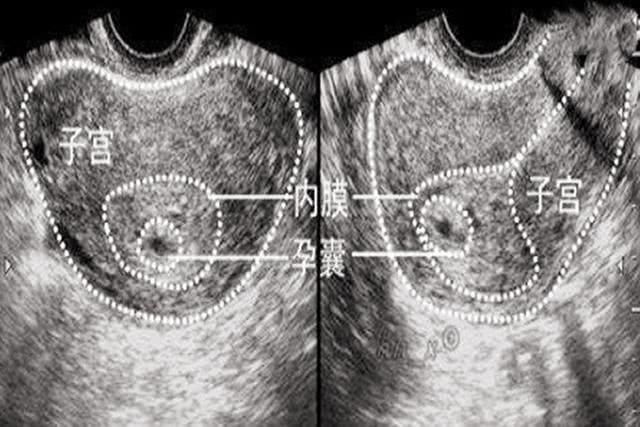

做B超的检查只要是看孕囊、胎心和胎芽。

1. 孕囊

观察孕囊主要看的是否在子宫内,也是最直观的判断是否是“宫外孕”的方式。

文章插图

只有孕囊在子宫内发育,才是正常的怀孕。而如果是在子宫外,那么就是宫外孕。宫外孕很容易引起孕期大出血,需要及时做手术处理,以免对身体健康造成伤害。